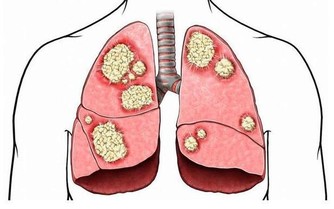

早期腸癌的臨床診斷率僅為11%-15%,治愈率高,術後5年生存率可達95%;而超過80%的患者確診腸癌時,

已發展至中晚期,治愈效果並不理想,5年生存率只有5%左右。

早期腸癌不疼痛,易被5種肛腸疾病掩蓋早期腸癌主要發生在腸粘膜上,基本無明顯的症狀。